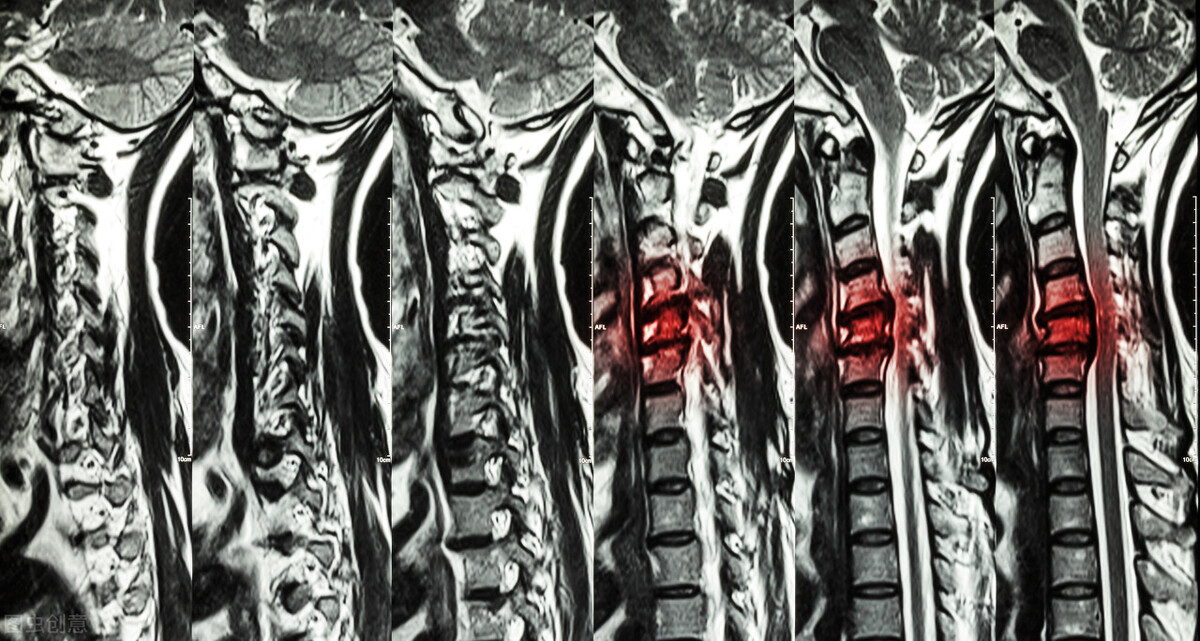

颈椎病患者CT